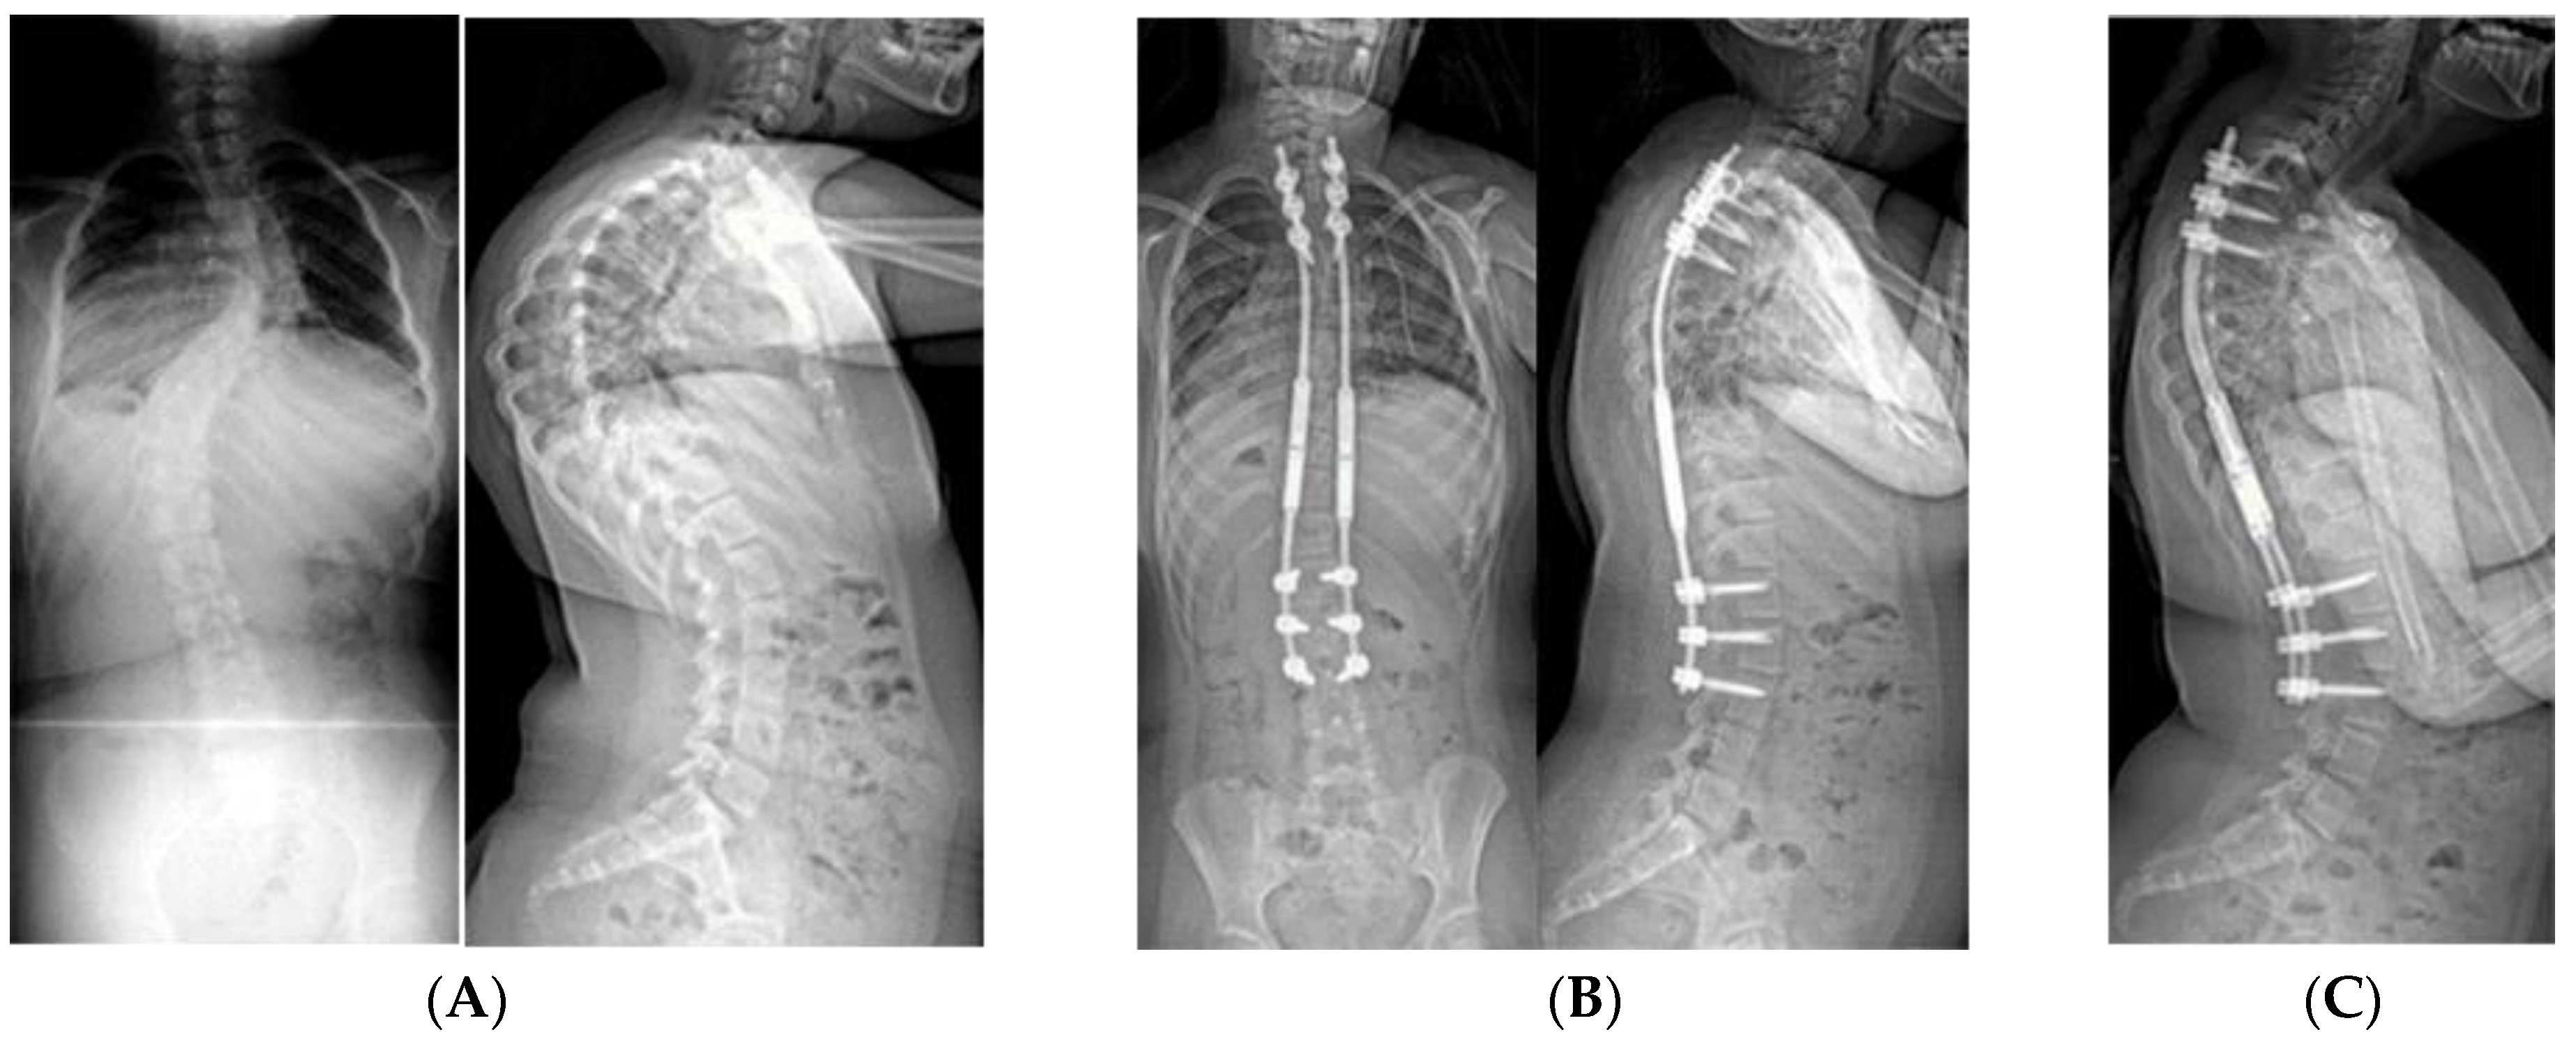

Young children with severe infantile curves may need stabilization of the spine to allow for more symmetric chest development with growth. Typically, these are child too old for spinal casting but have substantial remaining growth with curves >50° and minimal flexibility/improvement in brace. If they cannot be maintained in brace, then an expandable implant serves to internally splint the spine. Early implant versions required manual distraction, typically performed every six months as an open procedure in the operating room (Figure 8). This strategy worked well for controlling the curve and maintaining spine growth, but with the potential complications related to surgical procedures. In 2014, expandable spinal rods became available that were magnetically actuated through the skin. The rods are lengthened every three months, using an external spinning magnet, which causes the magnet within the rod to rotate thereby lengthening the rod (Figure 4). Oore et al found that the average initial curve was reduced from 76° to 42° at time of implant surgery with no change in curve size over the subsequent two years of rod elongation [40].

Figure 8.

(A) AP and lateral radiographs of a 10-year-old female with PWS deletion type with 103° curve. (B) AP and lateral radiographs 1 month later, after placement of non-fusion spinal instrumentation. Curve is 57°. (C) 18 months later, after 50mm of lengthening, curve is 25°.

Expandable implants, as a technique, have a life span of approximately five years, after which the ongoing process of spontaneous fusion along the section of the instrumented spine leads to stiffness and an inability to lengthen further [50,51]. Therefore, the goal is to manage the curve non-operatively until the child is 5–8 years of age, in order to “grow” the spine until at least 10 years of age. Unfortunately, the magnetically actuated rods only generate 42 pounds of axial force and may fail to generate enough force to elongate after several lengthening procedures. There are also issues related to titanium wear debris noted at the time of device removal [52]. Generally, these devices have made important improvements in the treatment of severe curves seen in young children with PWS. Usually, the construct is anchored with two vertebral levels above and below, but when there is any question of bone strength, three levels are fixated.

Spinal curves over 50° have a high propensity towards progression, even in skeletally mature patients; curves over 40° need to be closely monitored for progression. Timing of surgery can be tricky, adolescents with PWS experience delayed puberty, and females may not reach menarche or begin menses until in their 20s. PWS specific growth charts do indicate that boys and girls reach skeletal maturity essentially at the same age as their typically developing peers [53]. It is, therefore, preferable to delay spinal fusion until or after 12 years of age for females and 14 years for males. In general, teenagers with PWS have some concept of body image, but seem less perturbed by residual shoulder asymmetry or waist clefts. Achieving appropriate sagittal alignment is much more important in avoiding late deformity and assuring patient satisfaction. We try to limit our upper end vertebra to T3 or lower, even if still within the region of kyphosis; the rods are bent to accentuate kyphosis. Distally, the end vertebra is chosen much as it is for idiopathic scoliosis cases with a predisposition to fuse a level longer rather than shorter to prevent adding-on of the curve. The rods are bent to match or accentuate the pre-operative lumbar lordosis. Due to concerns of bone strength, nearly all included vertebrae are instrumented with pedicle screws bilaterally for better fixation (Figure 9).

Figure 9.

(A) 15-year-old female with PWS UPD type with 67° left thoracic and 60° right lumbar curve. She had thoracic kyphosis of 79° and lumbar lordosis of 84°. (B) Same patient at 4 years after T4–L3 posterior spinal fusion. The thoracic curve measures 12°, the lumbar 25° with 75° kyphosis.